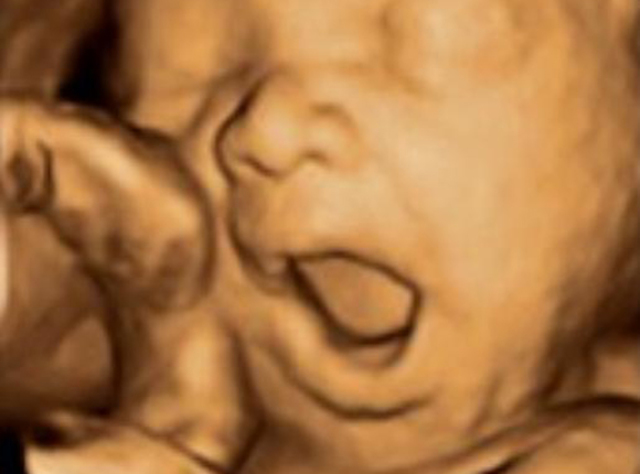

• Cuarto mes

Cuarto mes

Si hasta ahora lo importante era que los órganos se formaran correctamente, a partir de la semana 16 de embarazo el bebé tiene una misión importantísima: crecer y crecer. Y no para de moverse dentro del aún espacioso útero materno.